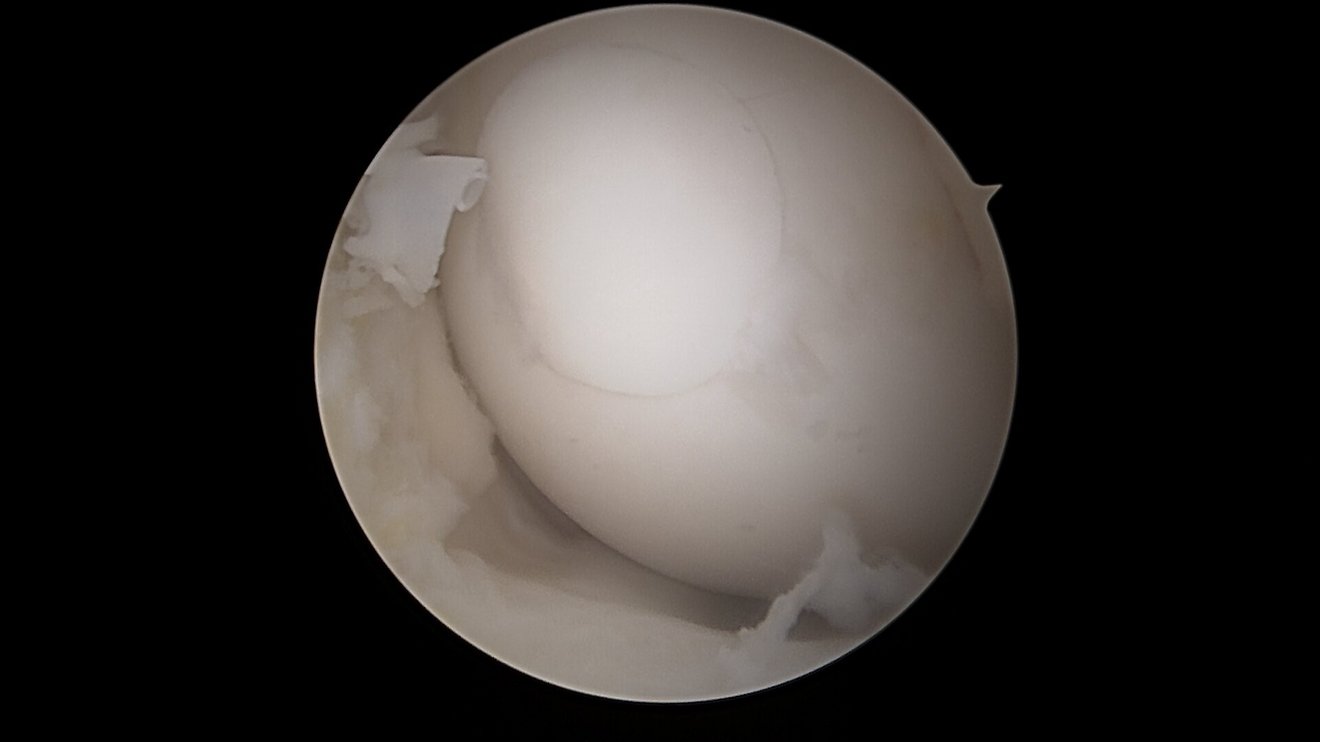

Eine der häufigsten Sportverletzungen im Bereich des Kniegelenkes ist die vordere Kreuzband-Ruptur. Vor allem bei jungen, sportlich aktivem Patienten ist oftmals eine sogenannte VKB-Ersatzplastik notwendig. Goldstandard ist der Ersatz des gerissenen Kreuzbandes durch eine körpereigene Sehne, ggf. können noch stehende Restfasern als Leitstruktur belassen werden. Hierzu stehen verschiedene Transplantate zur Verfügung (Hamstring-Sehnen, Quadrizepssehne, …) die individuell ausgewählt werden. Zusatzverletzungen des Meniskus oder der Seitenbänder werden ebenfalls im Rahmen der Operation behandelt. Das Kreuzband wird über Bohrkanäle an die anatomische Position gebracht und dort mittels sog. Interferrenzschrauben im Kanal verblockt.

Als Behandlungsmöglichkeiten für Knorpelschäden gibt es die sog. Abrasionschondroplastik / Mikrofrakturierung, bei der der defekte Knorpel bis auf den Knochen abgetragen und dieser dann mit kleinen Löchern perforiert und ggf. mit einer speziellen Membran bedeckt wird. Durch die Perforationen tritt Knochenmark in den Defekt ein und es bildet sich ein sog. Regeneratknorpel. Auch die Möglichkeit einer Knorpelzelltransplantation (sog. „ACT“) wird bei uns angeboten. Hier werden in einer ersten Operation Knorpelzellen entnommen und in einer zweiten Operation in den Defekt eingebracht (entweder als sog. ACT Inject in einer Suspension oder als ACT 3d auf einer Membran). Auch die körpereigene Transplantation eines Knochen-Knorpel-Zylinders (OATS / Mosaikplastik) ist eine Therapiemöglichkeit, die wir anbieten können.